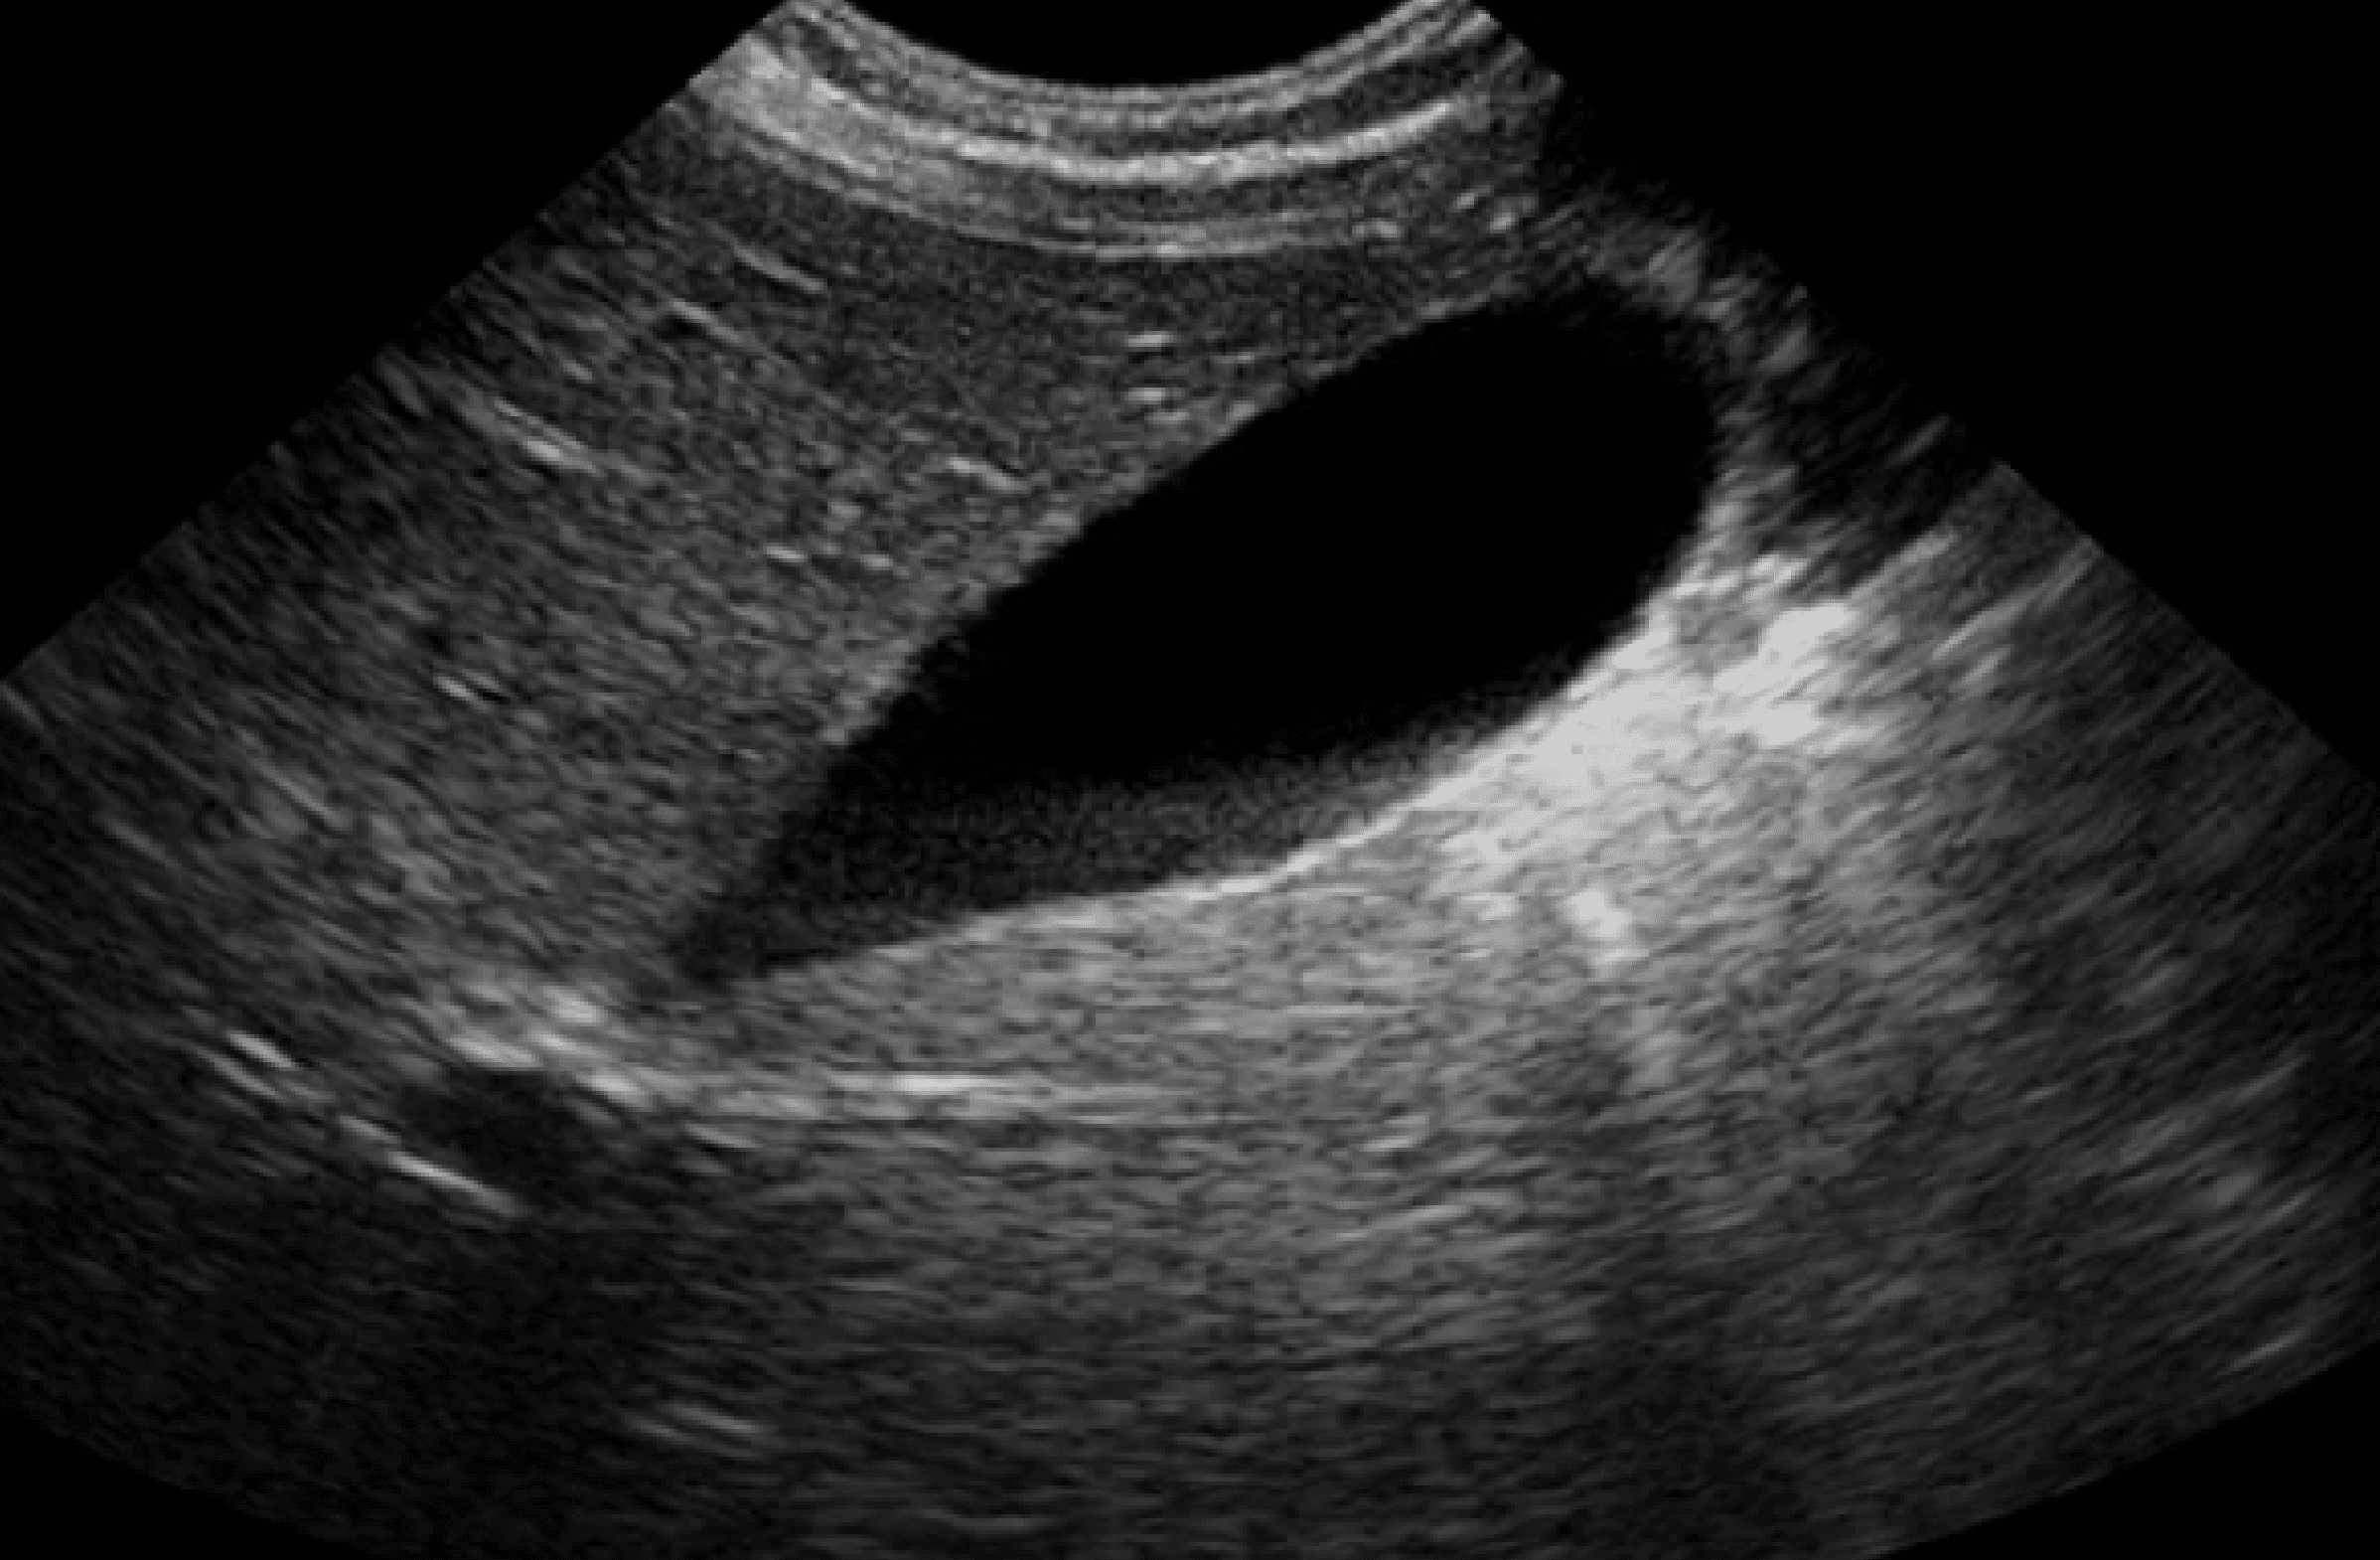

Auscultación rítmica sin soplos y con buena ventilación bilateral. Abdomen blando y depresible con dolor a la palpación en epigastrio sin peritonismo, ruidos presentes. Resto de la exploración por aparatos anodina. Se realiza una ecografía clínica abdominal sin alteraciones.